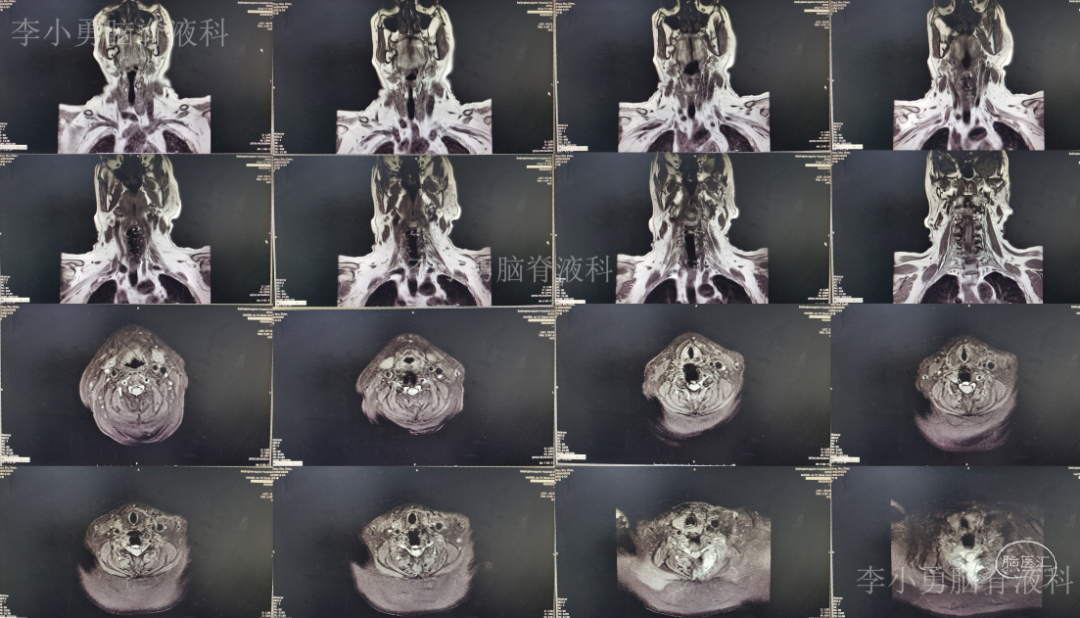

2020年8月13日(即第二次颈椎病术后第8天)患者开始出现颈部肿胀,床旁B超检查发现颈部切口深部积液,超声引导下穿刺抽出约87ml淡黄色透明液体,同时积液送细菌培养。2020年8月14日(即第二次颈椎病术后第9天)再次在床旁B超引导下穿刺抽液,抽出约90ml淡黄色透明液体,并加压包扎。复查颈部MR示术区皮下大量包裹性积液,考虑脑脊液漏(图-8)。

图-8:2020年8月14日颈部MR

2020年9月2日(入脑脊液科次日,即颈椎脑脊液漏修补术后第6天,即第二次颈椎病术后第25天)复查颈部MR示术区皮下深部仍有包裹性积液(图-10)。

图-10:2020年9月2日颈部MR